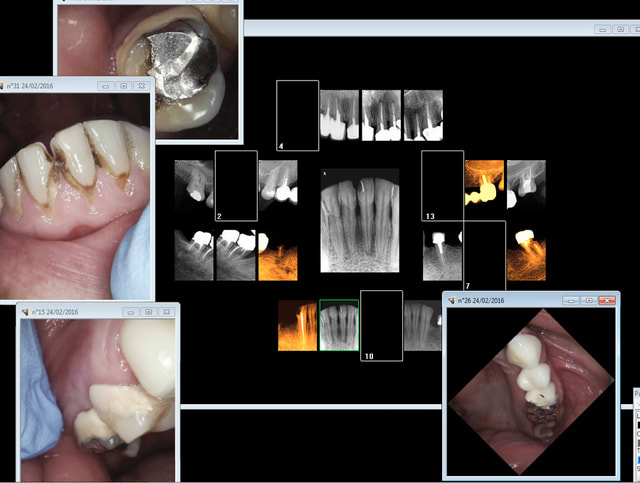

Oui, mais c'est pas pour le CDC ( il faut leur donner le moins d'informations possible, toujours la possibilité que ca se retourne contre soi) ) mais ca peut servir pour se défendre, si la procédure va plus loin que le simple entretien confraternel .

Exemple de justification :

justification de ce status : antécédents de soins intensifs + signes d'appels : douleur diffuse.